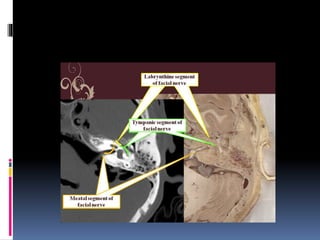

FACIAL NERVE:-